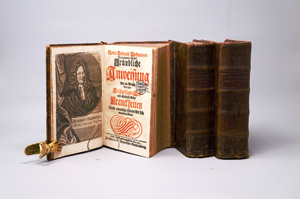

La Motte, Guillaume Mauquest de

Vollkommener Tractat von Kranckheiten schwangerer und gebährender Weibs-Persohnen

Zuschlag

160€ (US$ 182)